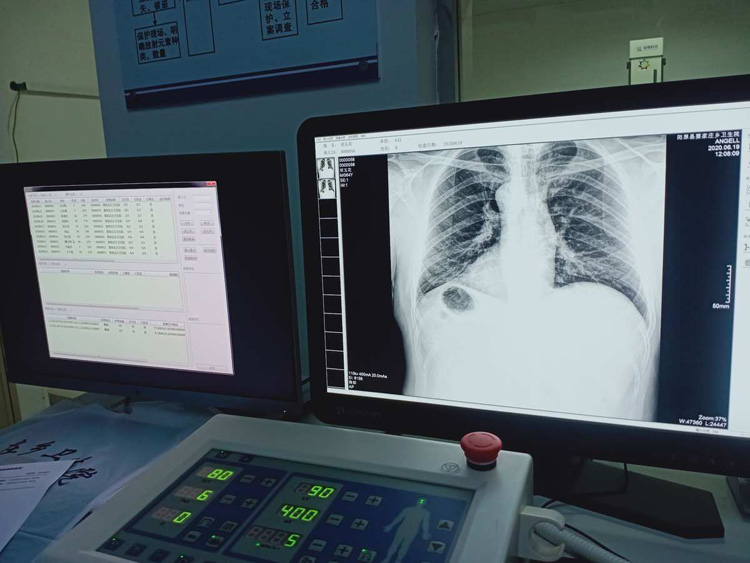

平床DR的平板探測器可以拍攝到高清的數(shù)字圖像。可以檢查身體的某個部位。頭部、胸部、腹部、上肢、下肢、正位、側位、都可以正常的拍攝。很小的劑量就可以采集到高清的檢查圖像。平板的穩(wěn)定性也非常的強。DR的平板探測器跟圖像結合。噪音低、圖像的畫質呈現(xiàn)豐富。圖像的信息量會跟多提供給醫(yī)生參考。幫助醫(yī)生提高診斷的準確性。Digital Radiography就是數(shù)字化拍攝。平板探測器特性會對拍攝片的圖片質量有關系。

平床DR的數(shù)字影像高分辨率,動態(tài)范圍比較大,密度密度分辨率高可以看到更多細節(jié)。拍攝的速度快偽影小。比X光的的靈敏度高很多。輻射小的能量就可以拍到清晰的圖像。輻射量少30%以上。特別是對骨頭軟組織的效果更優(yōu)。對結節(jié)的有沒病變的檢測查出率更高。